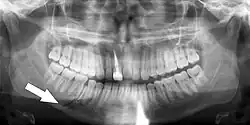

Panoramic radiograph

A dental panoramic radiograph, showing the maxilla and mandible, all the teeth including the "wisdom teeth," the frontal and maxillary sinuses, the nasal cavity and the temporomandibular joint and other near by head and neck anatomy. | |

A panoramic radiograph is a panoramic scanning dental X-ray of the upper and lower jaw. It shows a two-dimensional view of a half-circle from ear to ear. Panoramic radiography is a form of focal plane tomography; thus, images of multiple planes are taken to make up the composite panoramic image, where the maxilla and mandible are in the focal trough and the structures that are superficial and deep to the trough are blurred.